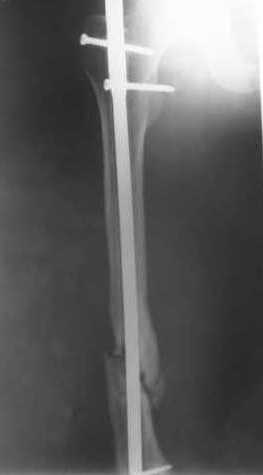

В приложении пример, как их использовали после остеотомии бедра по поводу сросшегося с вальгусом перелома, чтобы не дать гвоздю уйти во внутренний мыщелок.

Да, действительно красивый клинический пример: виден вальгус до операции и последующая коррекция углового смещения на "полярах". Я так понимаю, что в вашей клинике есть возможность использовать различные фиксаторы. Почему не использовали DFN? Спицы какие используете? Киршнера или Илизаровские? С виду очень тонкие...